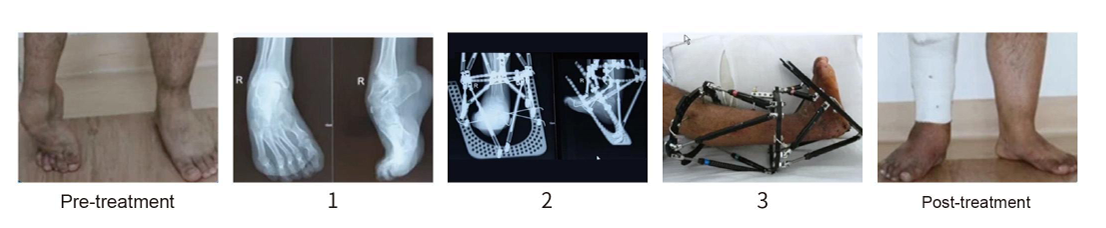

2.Deformity correction (including bone infection, nonunion, bone defects, limb lengthening, segmentdisplacement, correction of skeletal deformities, and complex foot and ankle deformities)